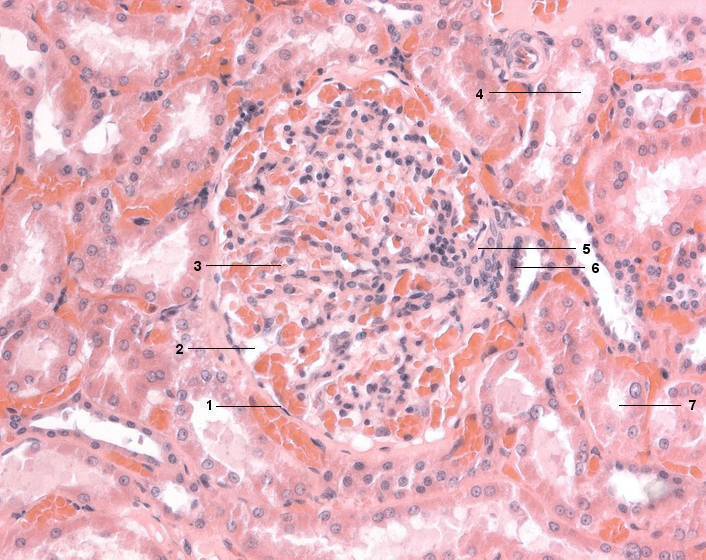

1 Bowman-Kapsel, parietales Blatt

2 Bowman-Kapselraum

3 Glomerulum, Kapillarknäuel

4 Distaler Tubulus

5 Gefäßpol, Polkissen

6 Macula densa

7 Proximaler Tubulus